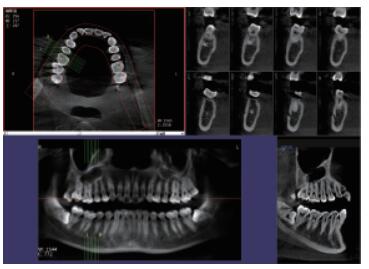

普愛口腔CT設(shè)備圖像質(zhì)量高產(chǎn)品說明:

運(yùn)用口腔CT進(jìn)行檢查可以大大提高口腔科臨床水平。以普愛醫(yī)療口腔CT為例,(它)可用于口腔種植、正畸、牙體牙髓、牙周、顳下頜關(guān)節(jié)、頜面外科及其他診斷需求,它有掃描速度快、成像速度快、操作軟件專業(yè)性強(qiáng)等優(yōu)點(diǎn),它可以輔助各種臨床診斷與治療??谇籆T產(chǎn)品特點(diǎn):

CMOS成像質(zhì)量優(yōu)

采用高端平板探測器,分辨率高、圖像質(zhì)量優(yōu)。

三維重建任意斷層

專有三維重建算法,可提供任意位置高清斷層影像。

高清口腔全景影像

通過三維容積影像,提取高清口腔全景影像。

專有圖像校正技術(shù),去除金屬偽影,提高圖像分辨率。

多平面組合重建

可同時觀察軸向面、冠狀面和矢狀面圖像,方便臨床診斷。